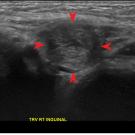

The causes of foot drop or lumps around the knee can sometimes be challenging to diagnose in the primary care or internal medicine setting. This article aims to describe one cause of both conditions.